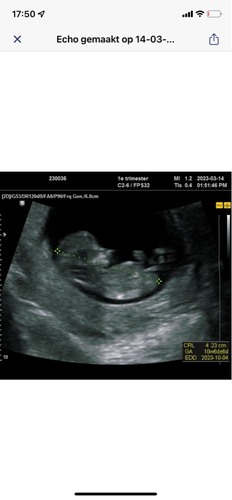

Dit was met 13 weken. Wie durft een gokje te wagen?

jomgen